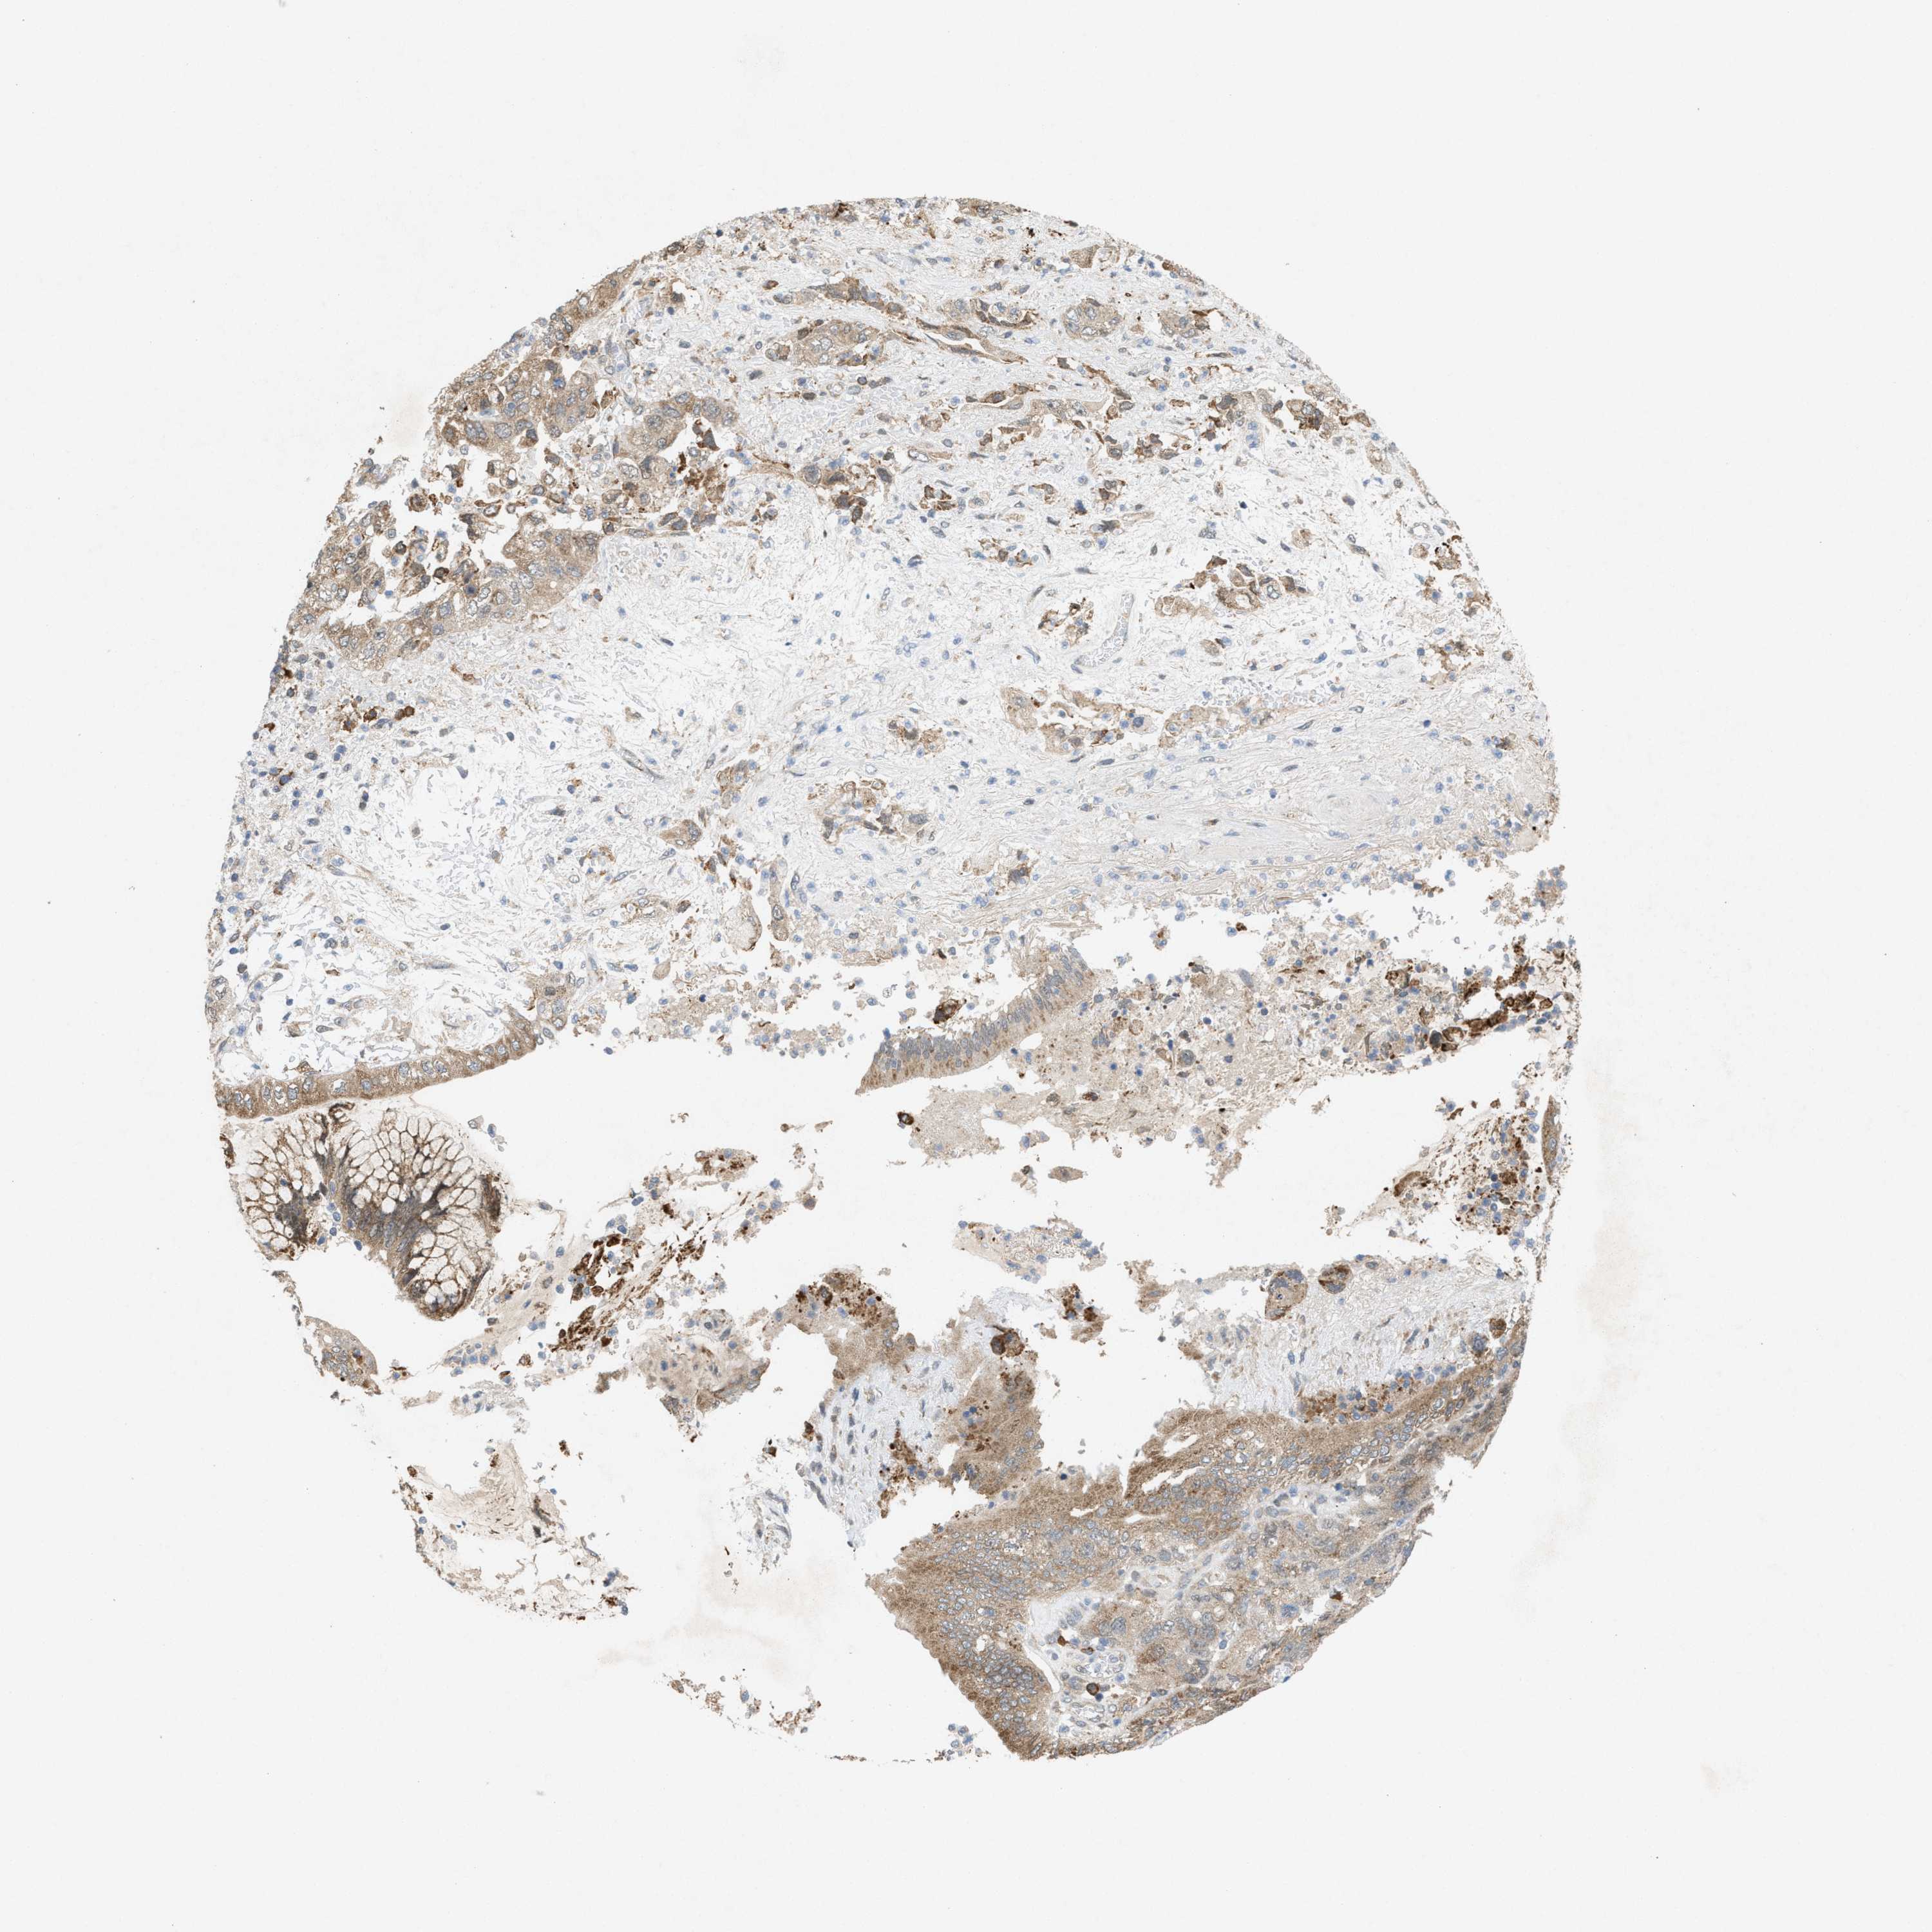

PANCREATIC CANCER - Protein expressioni

A mouse-over function shows sample information and annotation data. Click on an image to view it in a full screen mode. Samples can be filtered based on level of antibody staining by selecting one or several of the following categories: high, medium, low and not detected. The assay and annotation is described here.

Note that samples used for immunohistochemistry by the Human Protein Atlas do not correspond to samples in the TCGA dataset.

Antibody stainingi

Antibody staining in the annotated cell types in the current human tissue is reported as not detected, low, medium, or high, based on conventional immunohistochemistry profiling in selected tissues. This score is based on the combination of the staining intensity and fraction of stained cells.

Each image is clickable and will lead to virtual microscopy that enables deeper exploration of all samples and also displays staining intensity scores, fraction scores and subcellular localization as well as patient and tissue information for each sample.

Antibody HPA022274

Staining

High

Medium

Low

Not detected

Intensity

Strong

Moderate

Weak

Negative

Quantity

>75%

75%-25%

<25%

None

Location

Nuclear

Cytoplasmic/membranous

Cytoplasmic/membranous,nuclear

Adenocarcinoma, NOS